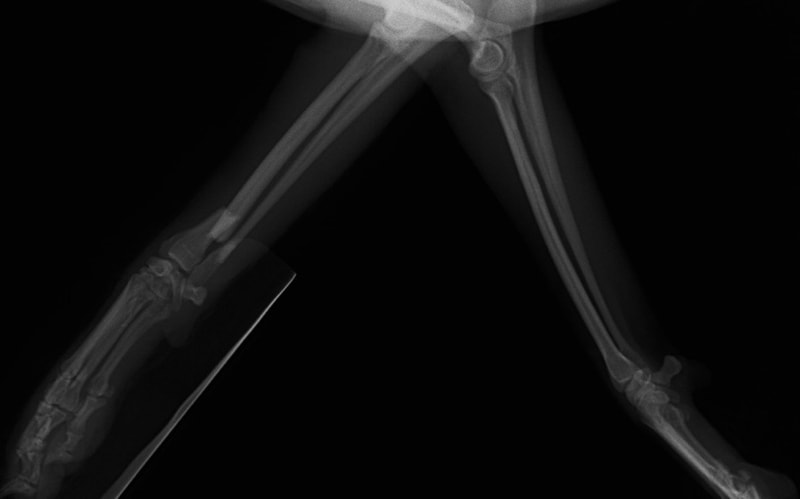

ペルシャ猫 11ヶ月齢 雄

他院にて左大腿骨遠位の成長板骨折(salter-harrisⅠ型)が認められており、治療相談を目的として来院。当院にて、キルシュナーワイヤーを用いたピンニングにより骨折部位の整復を行いました。術後の経過は良好で、現在も経過観察中です。

術前レントゲン